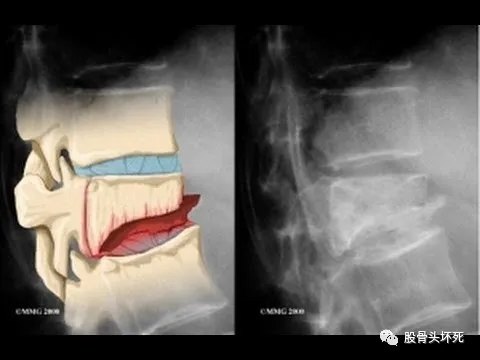

压缩骨折的放射学影响特征包括:一个或多个椎体前端楔形变伴椎体塌陷、椎体终板不规则和整体脱矿化。

椎体骨折的严重程度可按放射影像学表现分级:

●1级–脊柱高度降低20%-25%的畸形

●2级–脊柱高度降低25%-40%的畸形

●3级–脊柱高度降低>40%的畸形